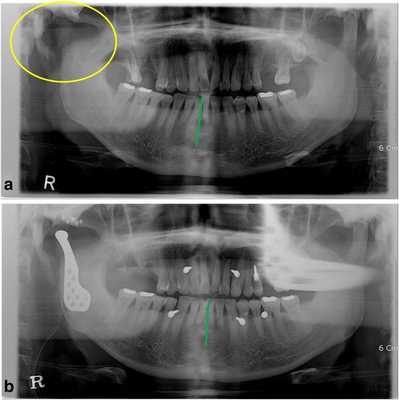

Фото 1.

а) Смещение нижней челюсти вправо (зеленая линия) в результате кондилэктомии (желтый круг).

b) Панорамная рентгенограмма, полученная через 1 день после операции, продемонстрировала восстановление окклюзионного соотношения (зеленая линия). Для стабилизации окклюзии во время операции были использованы межчелюстные фиксационные винты.

Диапазон раскрытия рта был ограничен расстоянием в 30 мм. После назначения пероральных антибиотиков с целью обеспечения инфекционного контроля была запланирована операция по реконструкции правого ВНЧС с использованием суставного протеза. Во время операции хирурги обеспечивали стабилизацию окклюзии путем межчелюстной фиксации для восстановления первоначального соотношения верхней и нижней челюстей. Установку суставного протеза проводили через два разреза: один - в околоушной области, другой - в подчелюстной по Risdon. Панорамная рентгенограмма, полученная через день после операции, подтвердила восстановление нормального окклюзионного соотношения (фото 1b). Через 3 дня пациента выписали без каких-либо осложнений послеоперационных осложнений, обеспечивая наблюдение на протяжении одного года. Протез функционировал достаточно хорошо, а восстановленная окклюзия оставалась стабильной, хотя максимальное открытие полости рта так и не удалось увеличить более чем до 30 мм.